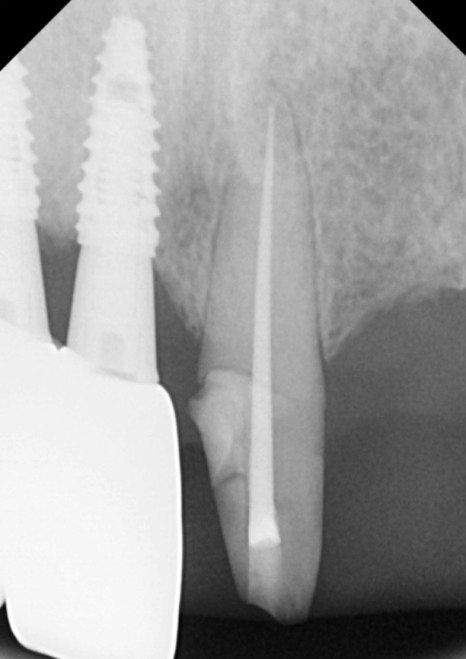

하지만 임플란트가 뼈와 붙기까진

시간이 필요하기에,

그동안 일상생활에 지장이 없도록

임시 치아를 예쁘게 만들어 드렸답니다. ^^

임플란트가 뼈와 단단히 붙기를

3개월간 기다린 후,

드디어 최종 보철물을 만드는 날이 왔습니다.